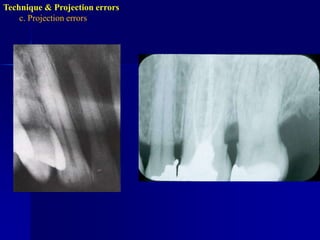

Technique & Projection errorsc. Projection errorsIncorrect horizontal angulationIs the appearance of the interproximal surfaces of the adjacent teeth over each other. This is due to improper H.A. due to improper alignment of the C.R. through the contact points i.e. not // to interproximal surfaces.

Technique & Projection errorsc. Projection errors

Technique & Projection errorsc. Projection errorsPID alignment artifactIf the PID is misaligned and the x-ray is not centered over the film, a partial image is seen on the resultant radiograph, this partial image is called cone-cut.It appear as a clear area with curved outline.